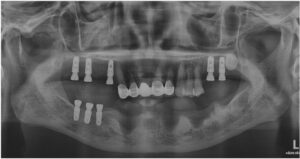

파노라마 촬영을 통해

임플란트가 정확한 위치와 방향으로

식립 된 것을 확인하였습니다.

아래턱 잔존 치아 발치 후

한 달 반 정도 지났을 때

충분한 뼈이식을 동반한

임플란트 식립을 진행하였는데요.

상실된 치아의 개수에 맞게

식립을 하면 가장 좋겠지만

처음 내원 당시 잇몸뼈 상태가

많이 좋지 않았었기 때문에

안정적으로 식립이 가능한 위치를 선정하여

식립을 도와드렸으며,

고정형 스크류를 통해

이식한 뼈가 단단히 자리 잡을 수 있도록

고정해 주었습니다.